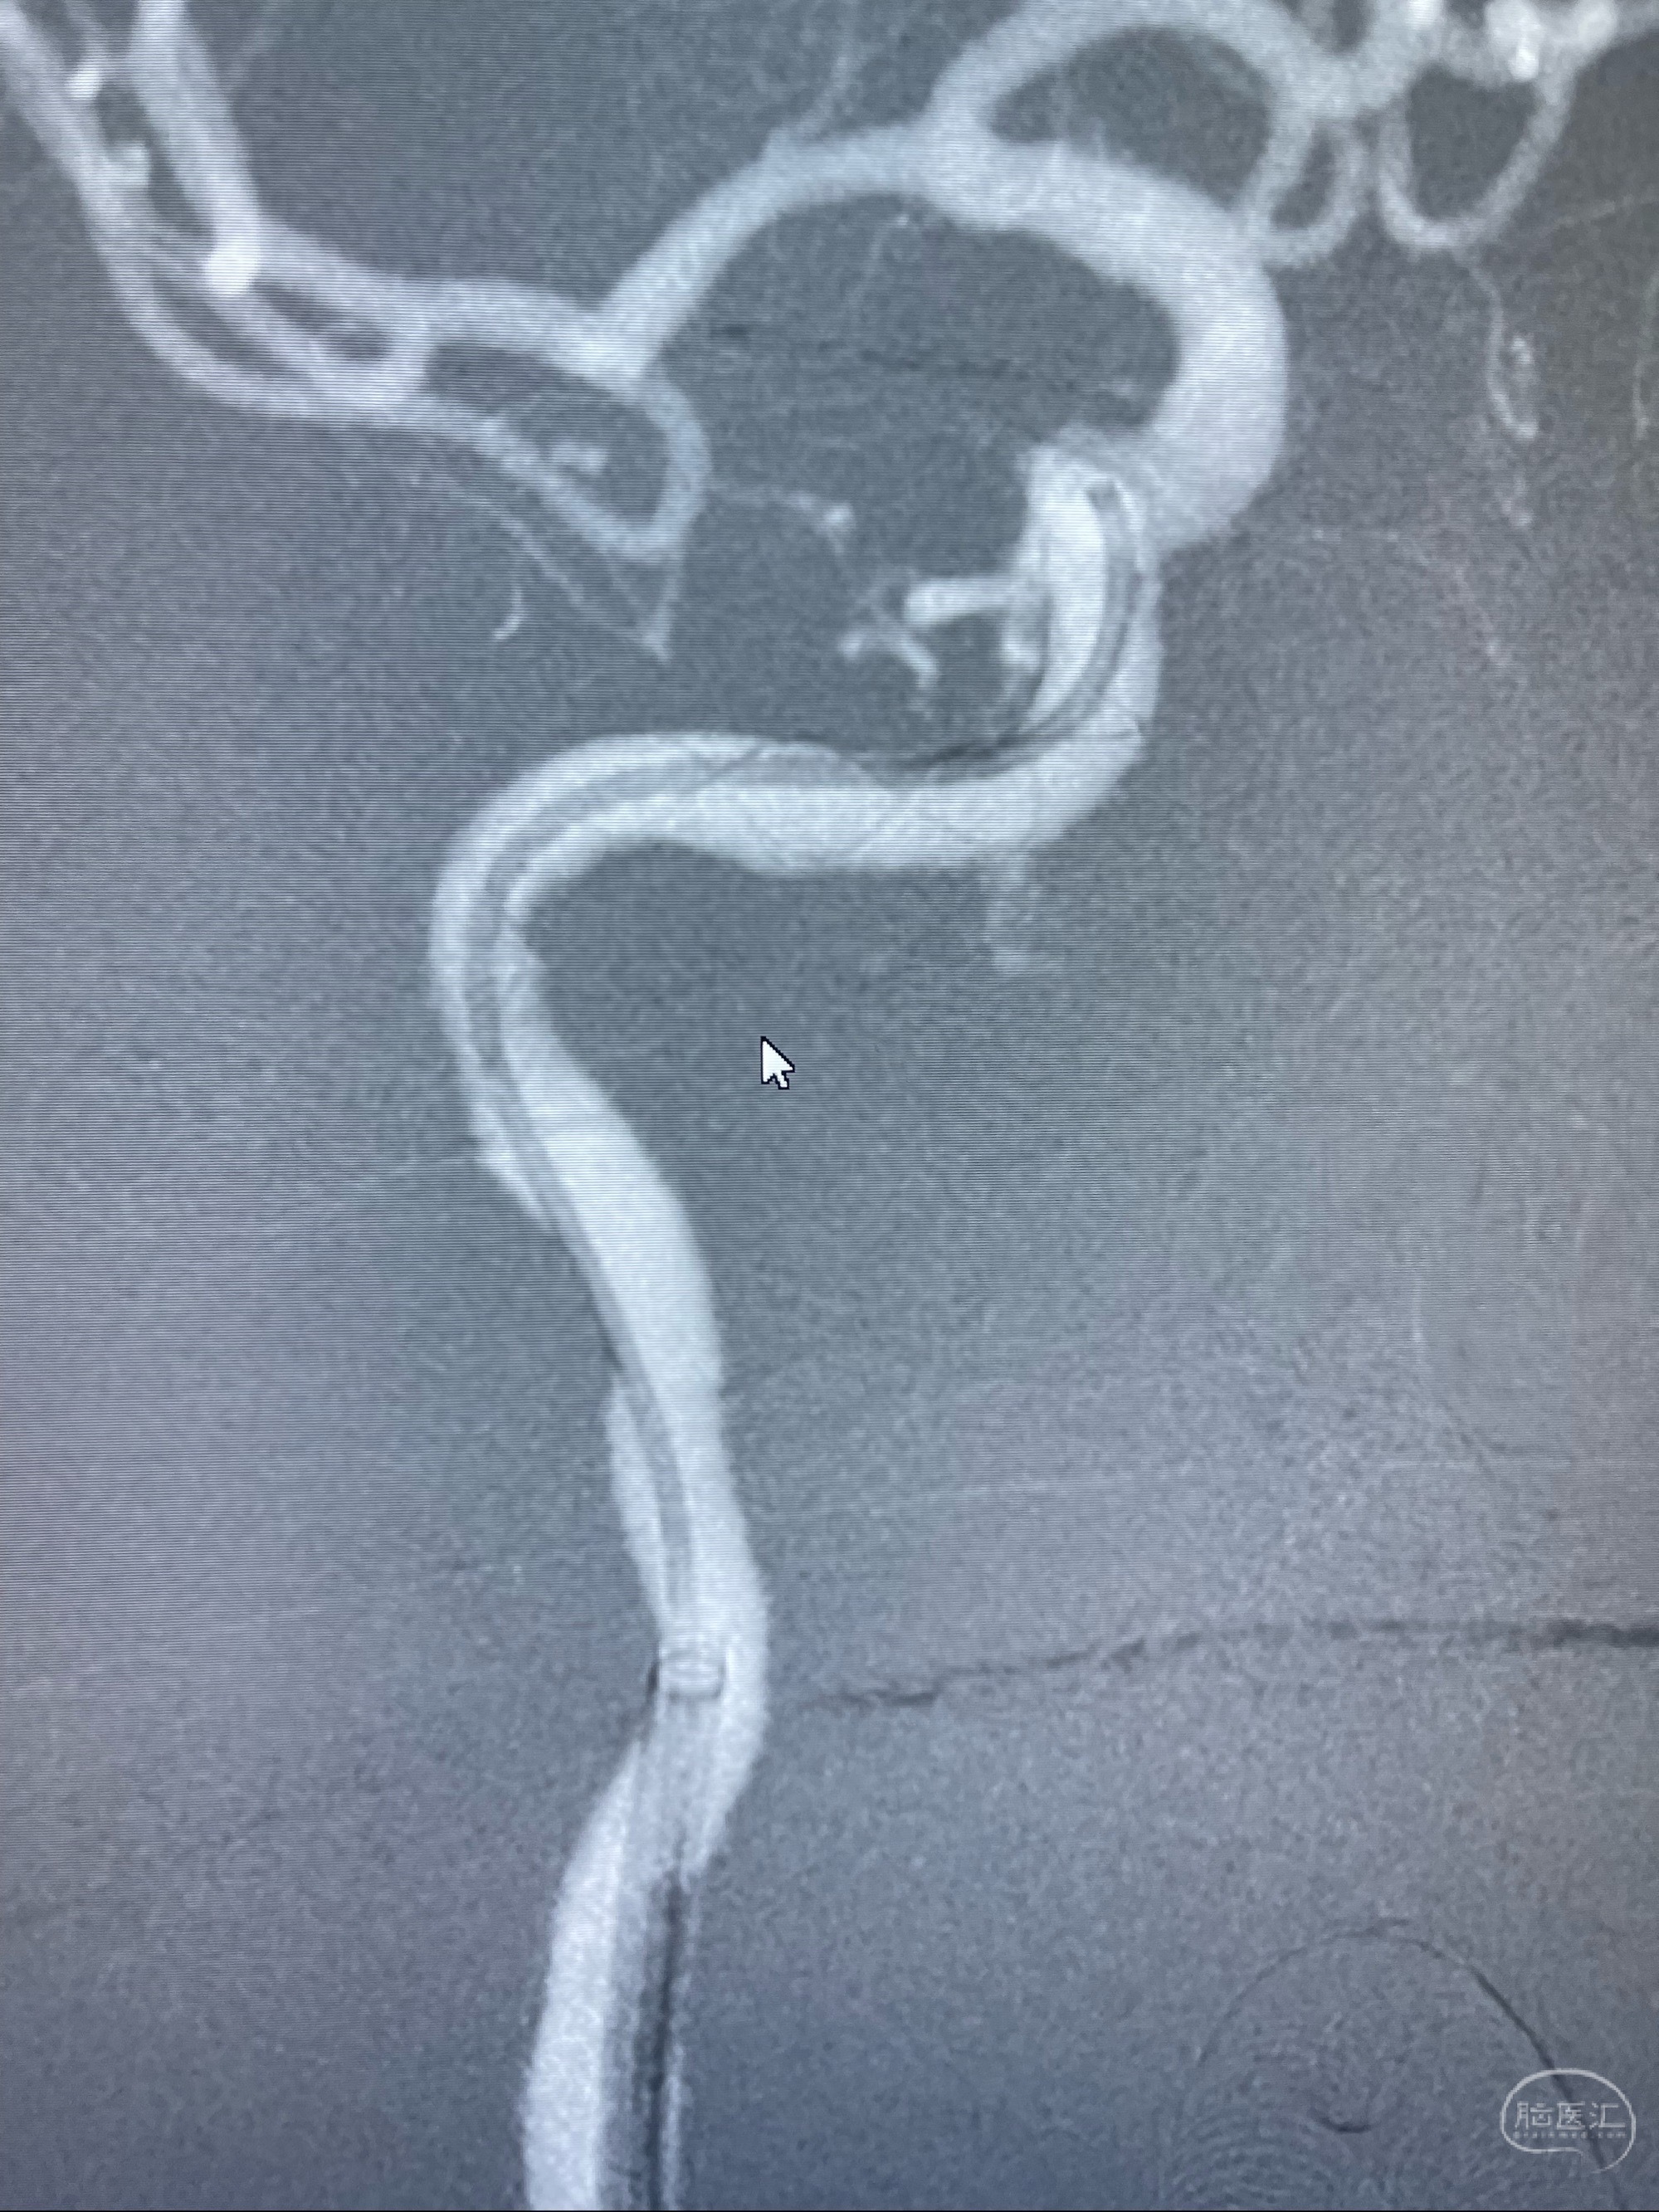

经导引导管造影显示支架远端颈内动脉不规则狭窄伴局部充盈缺损,同时行全身肝素化5ml

泄除球囊造影显示局部管腔扩张佳

即刻造影显示狭窄扩张佳

即刻造影显示支架贴壁佳

支架完全打开,近心端位于原颈动脉支架远心端内